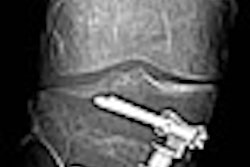

Another story deals with reducing radiation dose during percutaneous vertebroplasty procedures, in which interventional radiologists insert bone cement into the vertebra under fluoroscopic guidance. Researchers found that the use of a bone cement injector rather than a 1-mL syringe could cut radiation dose to the operator by more than half. Learn all about it by clicking here.